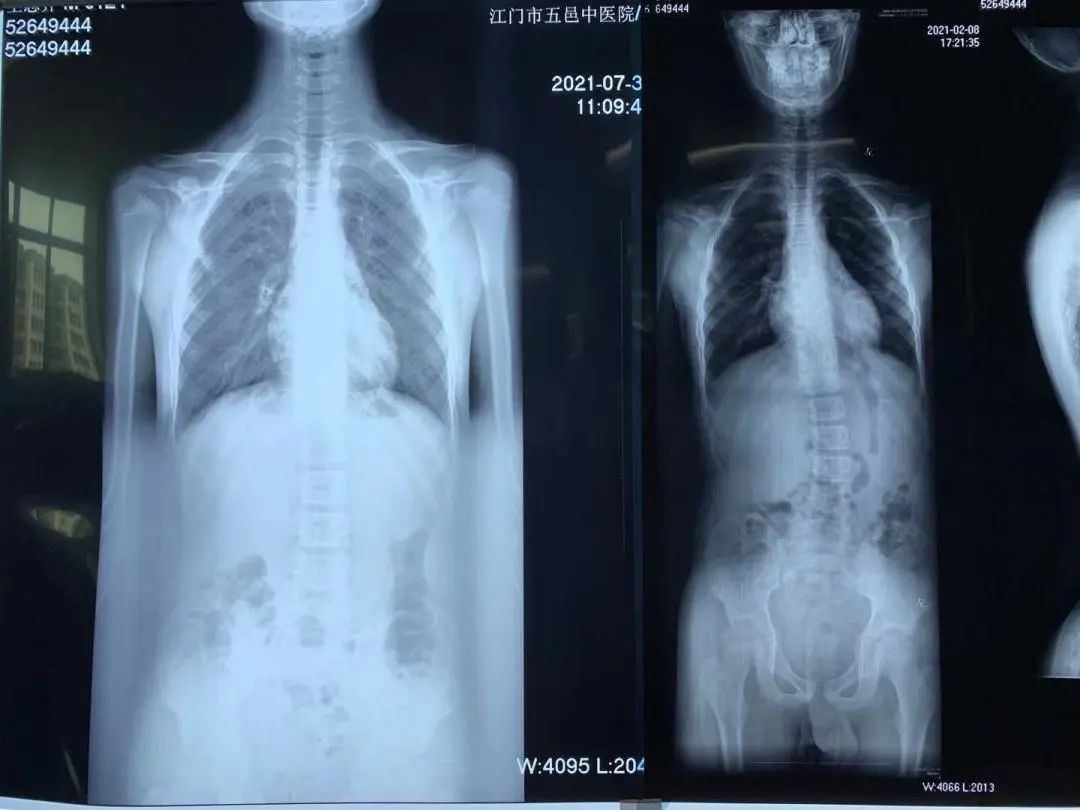

▲右图为半年前首次治疗,左图是半年后第二次训练营复查图